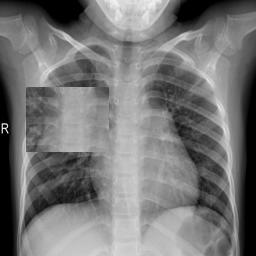

Large numbers of labeled medical images are essential for the accurate detection of anomalies, but manual annotation is labor-intensive and time-consuming. Self-supervised learning (SSL) is a training method to learn data-specific features without manual annotation. Several SSL-based models have been employed in medical image anomaly detection. These SSL methods effectively learn representations in several field-specific images, such as natural and industrial product images. However, owing to the requirement of medical expertise, typical SSL-based models are inefficient in medical image anomaly detection. We present an SSL-based model that enables anatomical structure-based unsupervised anomaly detection (UAD). The model employs the anatomy-aware pasting (AnatPaste) augmentation tool. AnatPaste employs a threshold-based lung segmentation pretext task to create anomalies in normal chest radiographs, which are used for model pretraining. These anomalies are similar to real anomalies and help the model recognize them. We evaluate our model on three opensource chest radiograph datasets. Our model exhibit area under curves (AUC) of 92.1%, 78.7%, and 81.9%, which are the highest among existing UAD models. This is the first SSL model to employ anatomical information as a pretext task. AnatPaste can be applied in various deep learning models and downstream tasks. It can be employed for other modalities by fixing appropriate segmentation. Our code is publicly available at: https://github.com/jun-sato/AnatPaste.